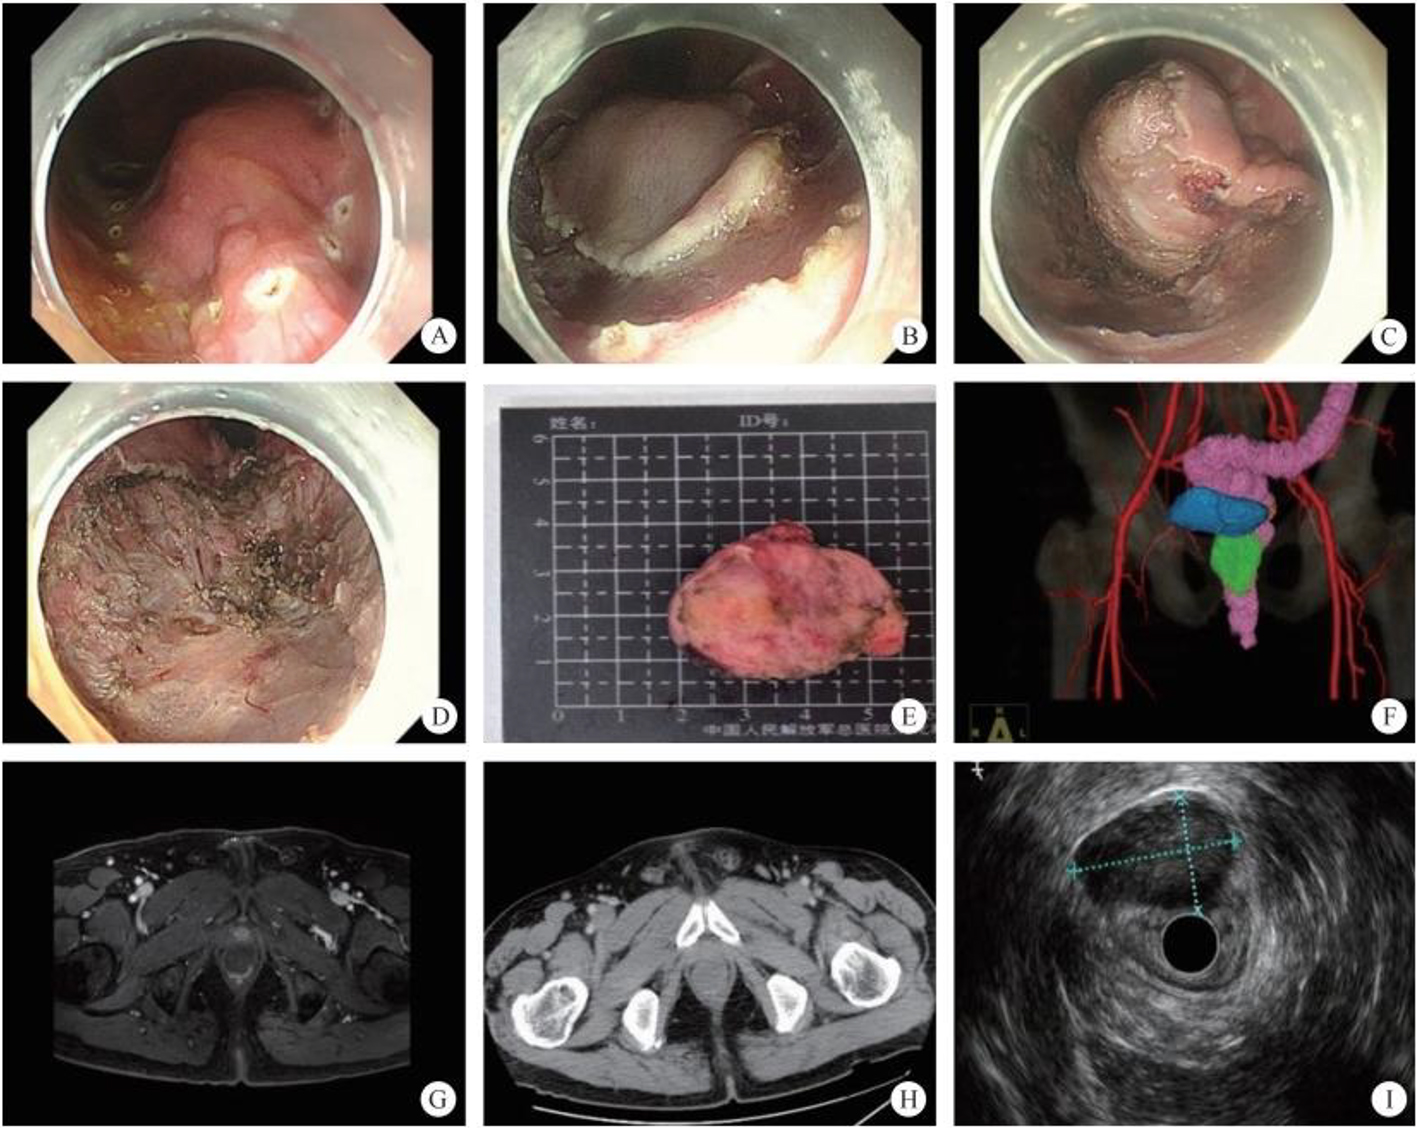

4. Development of the multi-cavity channel. As part of multidisciplinary treatment in the age of precision medicine, combined endoscopic surgery will create chances at sites where the single endoscope does not know what to do, to provide convenience to positions where treatment is difficult. Over the recent 10 years, development of this direction has focused on the endoscopic combined with laparoscopic treatment of upper gastrointestinal stromal tumors and refractory colon polyps. The surgical modes include laparoscopy-assisted endoscopic full-thickness resection (LAFEFR), laparoscopic and endoscopic cooperative surgery (LECS), etc. In the future, developments in this direction will challenge traditional surgical techniques. Endoscopic digestion combined with laparoscopic bi-endoscopic lesion resection + lymph node dissection will further expand the SMIS therapeutic indications in the field of gastrointestinal cancer.

Gastrointestinal endoscopic super minimally invasive surgery (eSMIS) is a branch of SMIS operations. After multiple years of development and clinical practice, presently eSMIS has a perfect endoscopic technique, a nomenclature of procedures and implementation principles, as well as specific development perspectives. Over the recent 10 years, endoscopic scholars in China have been constantly innovating and developing a series of SMIS surgical methods according to four directions, namely, natural, tunnel, puncture, and multi-cavity channels. For example, in the SMIS operation of early gastric cancer, full-thickness resection of the lesion by natural channel, full-thickness resection by multiple-cavity + lymphadenectomy approaches, the technique of sealing large wounds after non-full-thickness resection, and the traction technique in non-full-thickness resection; in the treatment of large-area early esophageal cancer by tunnel channel, autologous skin graft was used to prevent esophageal stenosis after large esophageal defect, and for the diagnosis and treatment through the muscularis propria to the outside of the digestive lumen; some breakthroughs in SMIS operations of the bile pancreatic disease, including laser lithotripsy under direct choledochoscope with sphincter preserved, exploratory pancreatic duct with cholangiopancreatic vision system, super minimally invasive photodynamic therapy under pancreatoscope, radiofrequency ablation of bile duct under direct choledochoscope, direct choledochoscopy with a duodenal papillary support for the extraction of gallbladder silt stones and of biliary calculus, etc., have been achieved.